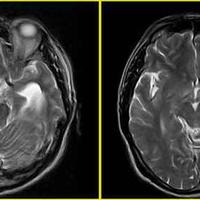

这名少年正在一个综合性的外科癫痫中心接受

这名少年正在一个综合性的外科癫痫中心接受医学上难治性癫痫的治疗。立体定向深度电极(立体定向脑电图)的植入被放置在假定癫痫发作的区域——在这种情况下,右半球覆盖了...

结节性硬化症 (TSC) 是一种常染色体

结节性硬化症 (TSC) 是一种常染色体显性遗传的神经皮肤病,具有完全外显率,但临床表现极为不同。超过一半的病例是由具有阴性家族史的个体的自发突变引起的。灰叶斑...